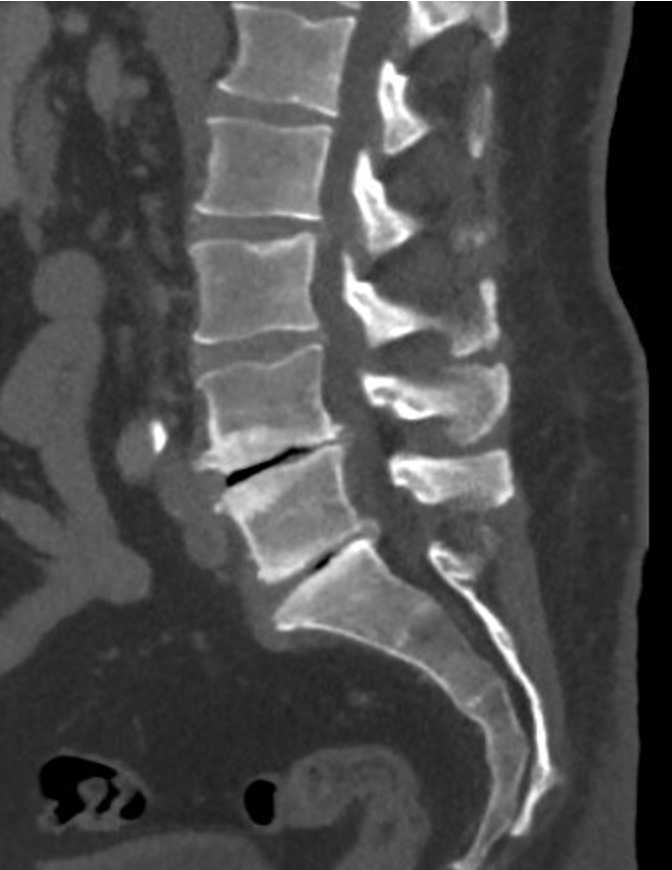

A lumbar spine X-ray showing a normal disc and a degenerated disc with labels pointing to each.

• Not always. MRI is usually recommended when symptoms persist or worsen.

• X‑rays can show certain changes such as disc height loss, and bone spur formation. They do not show nerves.

However, X-rays are also important because they can show your bone alignment and possibly other issues that are not shown on MRI.

• Not always. Imaging findings and symptoms do not always match.